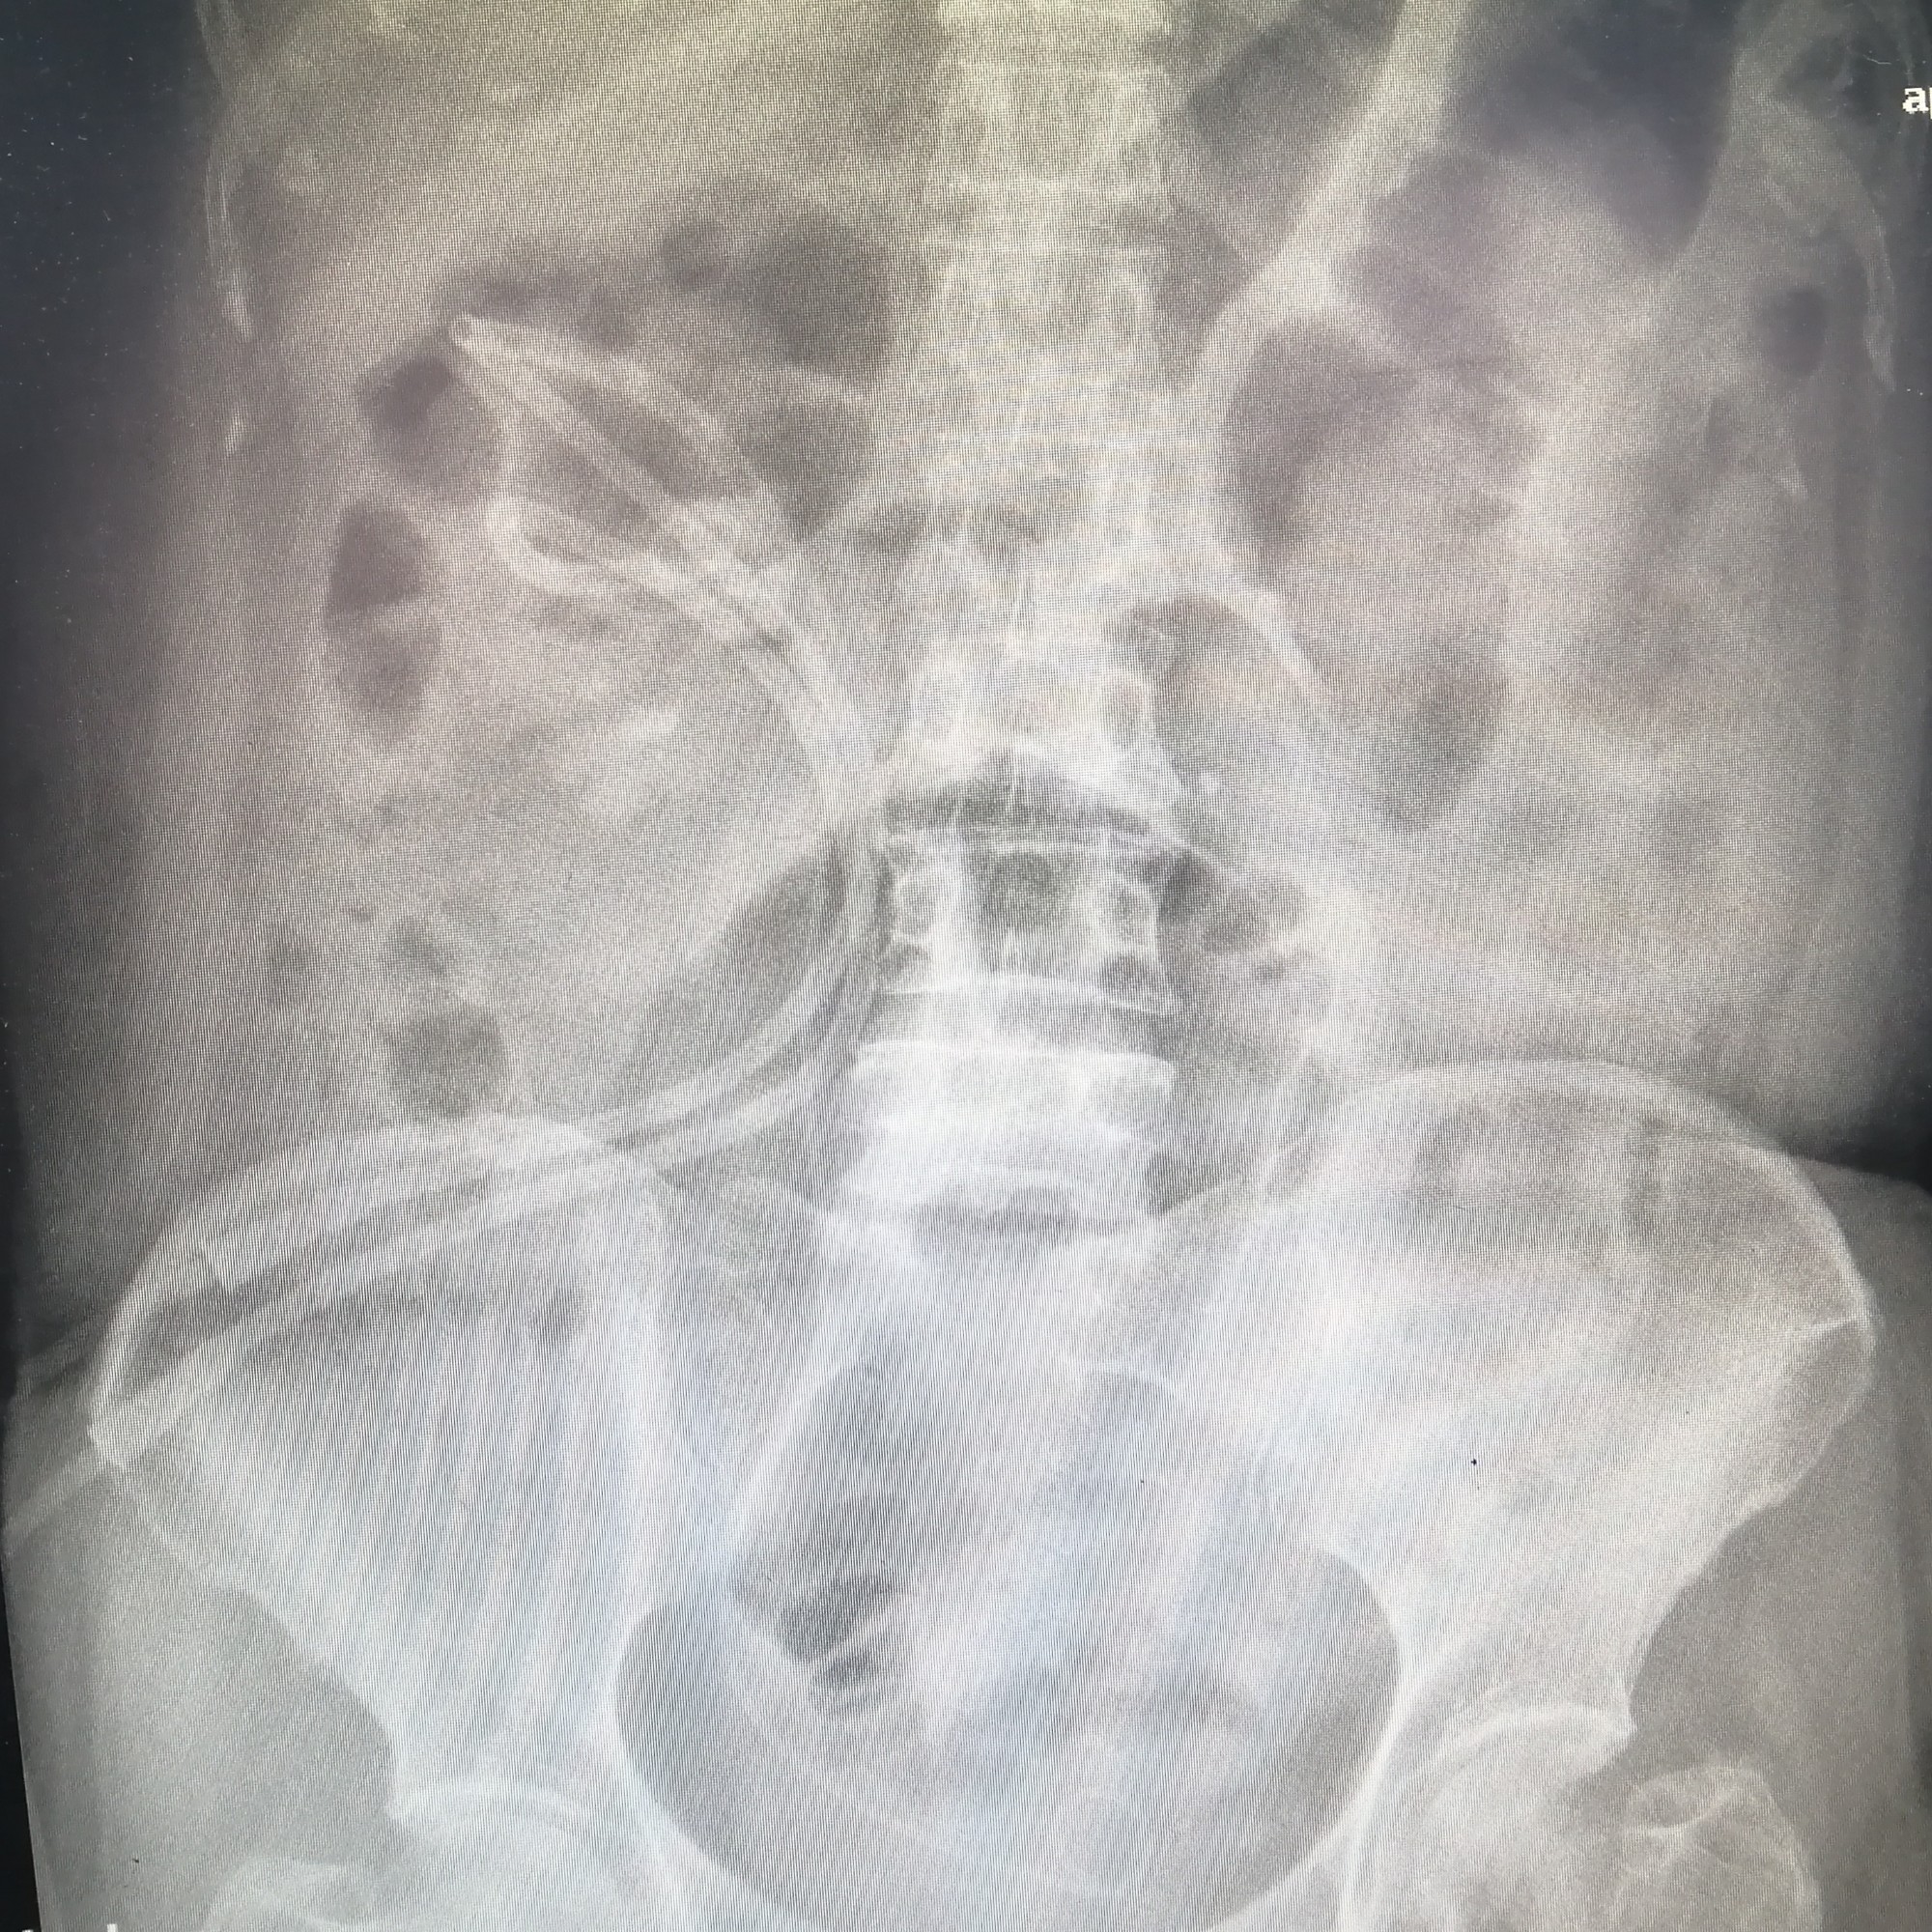

接受“碎石航母”治疗的首例患者是55岁的王女士。长期以来,王女士饱受腹部疼痛的困扰,来医院检查后,影像学资料显示王女士肾结石最长直径约9cm。在与患者及家属沟通后,王女士主动选择使用第五代EMS治疗,于是在开机当天,泌尿外科团队成功为王女士完成结石手术。3月26日,王女士复查影像学结果显示,结石已全部清除干净,且术后效果良好。